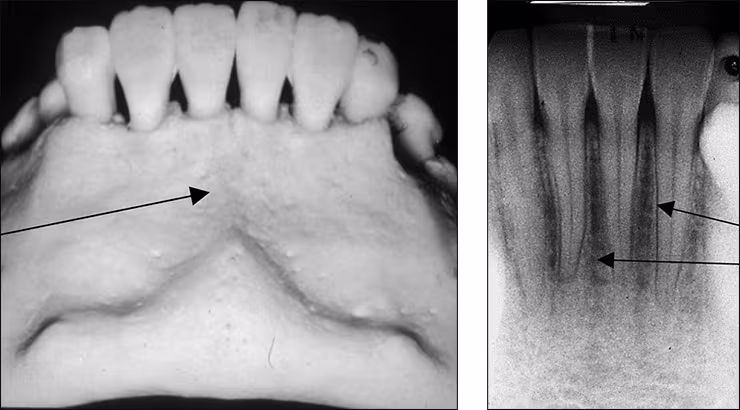

Genial tubercle – The genial tubercle is a spiny protuberance or prominence (sometimes two) of bone located in the midline on the lingual aspect of the mandible below the roots of the incisor teeth. This structure serves as the locus of attachment for the genioglossus and geniohyoid muscles. Although variable in appearance, the tubercle often produces a ring-like or doughnut-shaped radiopacity on mandibular incisor periapical images. The genial tubercle is also referred to as the mental spine.

Lingual foramen – The lingual foramen is a small pin-point opening in bone on the lingual aspect of the anterior mandible for the lingual nerve and arteries. The lingual foramen appears in the midline below the apices of the central incisor teeth. This dot-like radiolucency is frequently surrounded by the genial tubercle. The lingual foramen is recorded on mandibular incisor periapical images.